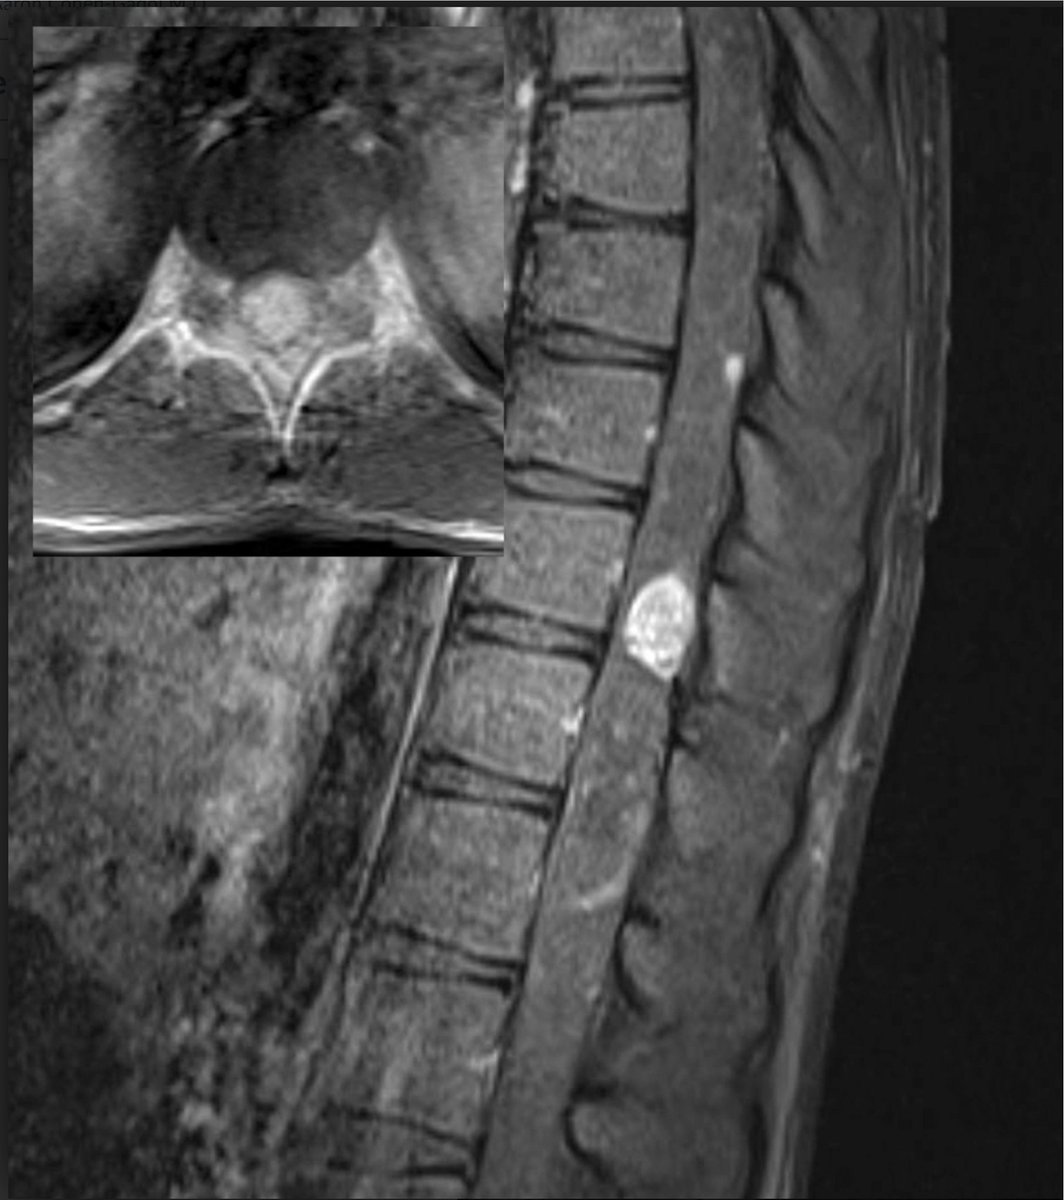

#MCWNeuroradBTW 095:Headache